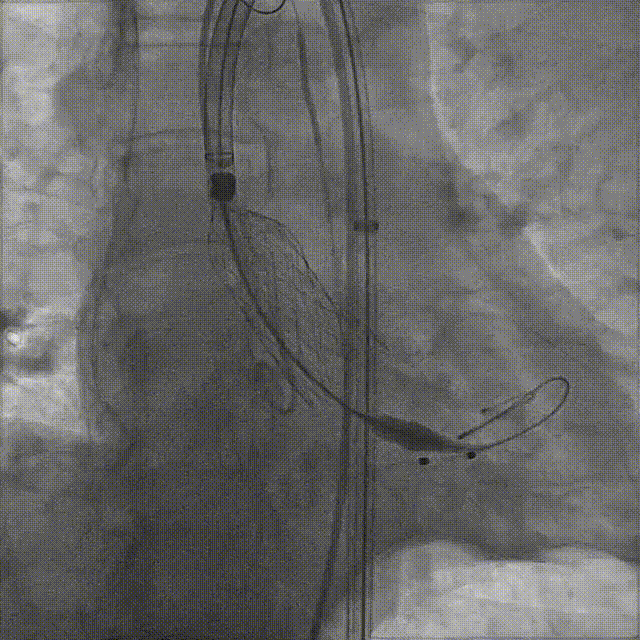

袁祖贻院长 西安交通大学第一附属医院 创新见证中国领跑,数据积累筑牢临床效果 韩克教授 西安交通大学第一附属医院 干瓣技术革新赋能特殊人群治疗,“量体裁衣”筑牢安全防线 患者病史 主诉与现病史:5年前因"血友病,血尿”就诊于当地医院,住院期间行心动超声提示主动脉瓣及二叶瓣畸形,无胸闷气短,无胸痛,咳嗽咳痰,无头晕,恶心呕吐等不适。未予以干预,后规律复查心超,3周前复查心超提示:主动脉瓣二瓣化畸形并重度狭窄,升主动脉内径明显增宽。 既往史:确诊血友病A型40年 术前超声提示:先天性主动脉瓣二叶式畸形,主动脉瓣中度狭窄,升主动脉增宽,左室舒张功能减低,EF73% 术前CT:Type0型二叶瓣,瓣叶增厚无钙化,主动脉瓣环径24.1mm,LVOT23.9mm;双侧冠脉开口高度可,窦部空间可,STJ、升主动脉内径可;预估冠脉低风险;主动脉水平夹角37.1°,主动脉弓角、弓距可;左室内径可;外周入路无明显迂曲,无钙化;双侧股动脉内径可,右侧股动脉低分叉。 手术策略 推荐右侧股动脉为主入路,左侧股动脉为辅入路。右股分叉上方1mm穿刺;仅舒张期时相,需根据球扩结果评估瓣膜尺寸,推荐使用18mm球囊进行预扩;预装AV26瓣膜。 手术过程 在右股动脉穿刺建立通路后,顺利送入大鞘。18mm球囊预扩后评估无腰无漏,后将Prostyle A® AV26瓣膜精准释放于目标位置,术后即刻造影显示无明显反流,无瓣周漏,平均跨瓣压差由术前的100mmHg降至2mmHg,患者血流动力学显著改善,术后超声证实瓣膜启闭良好。 主动脉根部造影 18球囊预扩 定位 稳定释放后脱钩 最终造影形态位置良好 外周血管造影,无血管并发症 术后超声显示无生物瓣位置固定瓣膜功能正常,无瓣周漏。 Prostyle A®预装干瓣——助力临床最优化解决方案 流入端桶状设计:流入端桶状的设计,锚定迅速,有效减少释放步骤,提升植入稳定性; 平衡的收腰设计:二叶瓣患者对瓣膜径向支撑力提出更高要求,Prostyle A®均衡的收腰设计可更好适应二叶瓣解剖,保证了EOA,有效降低了循环崩溃风险,提高瓣膜的耐久性; 预装干瓣 便捷顺安:金仕生物专利抗钙化技术运用纳米技术去除组织内的细胞碎片和磷脂,封闭游离醛基,从根本上阻断了瓣膜钙化的多项因素,显著提升了瓣膜的耐久性;同时,相比较传统戊二醛保存方式,干式存储最大限度的保留心包的亲水亲油平衡,还原组织天然曲柔性,进一步保障了瓣叶开合,保证长期耐久性。 专家简介 袁祖贻 西安交通大学第一附属医院(点击查看专家详细简历) 韩克 西安交通大学第一附属医院(点击查看专家详细简历) · END ·